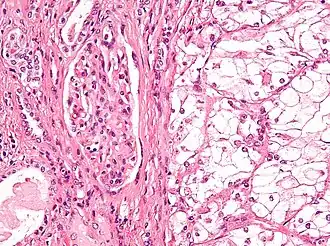

![]() Micrografía que muestra el tipo más común de cáncer de riñón (carcinoma de células renales de células claras). Tinción H&E. | ||

El tipo más común de malignidad renal es el carcinoma de células renales,[33] que se cree que se origina en las células del túbulo contorneado proximal de la nefrona.[15][34] Otro tipo de cáncer de riñón aunque menos común, es el cáncer de células de transición (CCT) o carcinoma urotelial de la pelvis renal.[35] La pelvis renal es la parte del riñón que recoge la orina y la drena en un tubo llamado uréter.[35] Las células que recubren la pelvis renal se denominan células de transición y, a veces, también se denominan células uroteliales. Las células de transición/uroteliales en la pelvis renal son el mismo tipo de células que recubren el uréter y la vejiga. Por esta razón, el CCT de la pelvis renal es distinto del CCR y se cree que se comporta más como el cáncer de vejiga.[35] Otros tipos raros de cáncer de riñón que pueden surgir de las células uroteliales de la pelvis renal son el carcinoma de células escamosas y el adenocarcinoma.[15]